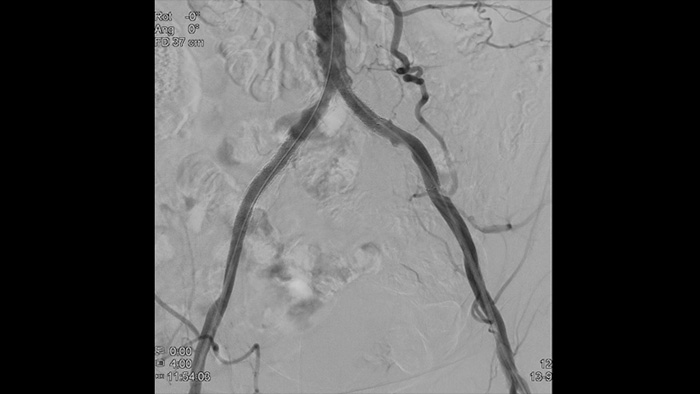

Nosso pacote Vascular fornece opções de fluxo de trabalho, ferramentas intervencionistas dedicadas e uma ampla seleção de dispositivos vasculares avançados para aumentar a eficiência dos procedimentos e redefinir os desfechos para seus pacientes portadores de doença aórtica, facilitando todas as etapas do seu procedimento — à medida que você decide, orienta, trata e confirma os resultados do tratamento.

Com o Azurion da Philips, ocorreu uma revolução em termos de aprimoramento do fluxo de trabalho que resultou em uma eficiência comprovada. Com o número sempre crescente de pacientes com doença aórtica, o Azurion oferece uma série de inovações no fluxo de trabalho projetadas para ajudar as equipes vasculares a trabalhar de forma eficiente e consistente e, ao mesmo tempo, manter um foco único no paciente e gerenciar a dose de radiação durante as intervenções.